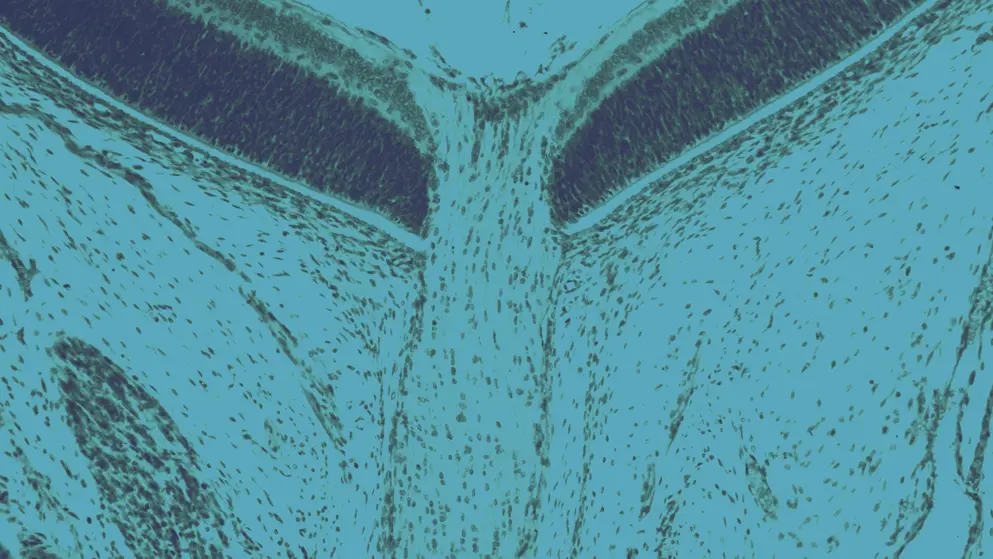

Glaucoma is a group of progressive eye diseases that damage the optic nerve, typically due to increased intraocular pressure (IOP). The most common types include primary open-angle glaucoma and angle-closure glaucoma, each with distinct pathophysiological features. IOP rises when aqueous humor accumulates in the anterior chamber, typically due to impaired drainage. As pressure builds, it compresses the optic nerve, gradually leading to vision loss. Although glaucoma is a leading cause of blindness in adults over 60, timely diagnosis and management can preserve vision.